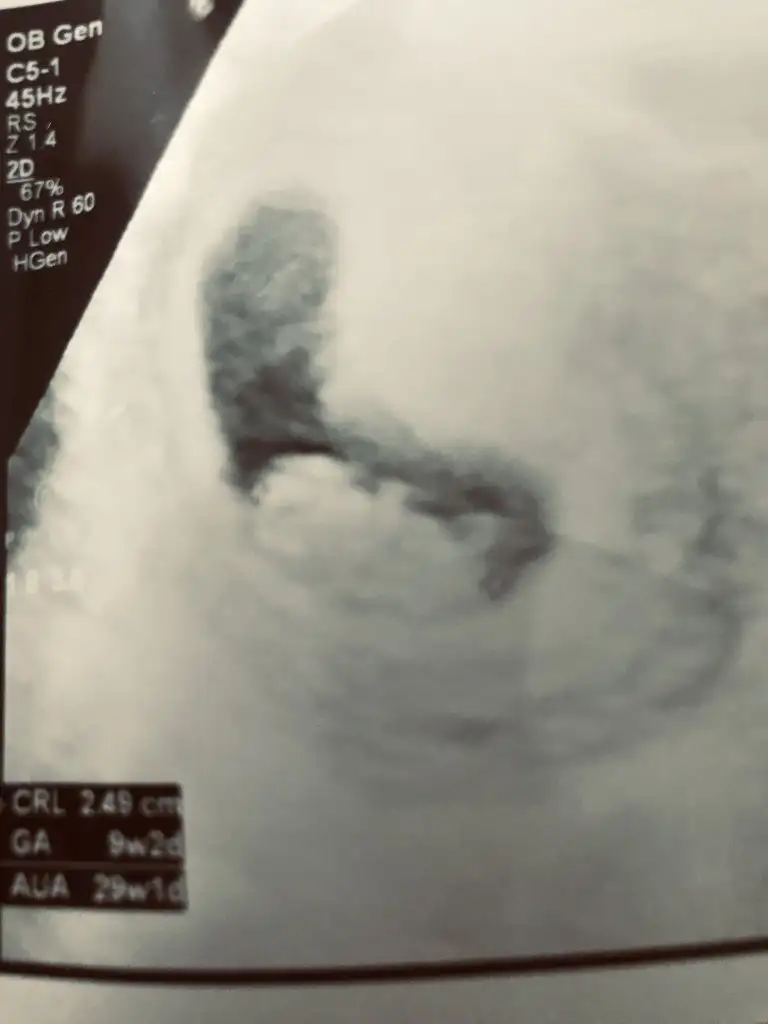

Evet erken en iyi 11 12 13 haftalar olmalı USG 9 haftalık sanırım.Bir yorumda ben alabilir miyimBiraz erken ama

11 12 13 haftalar olmalı9+2 rica etsem tahmin yürütür müsünüz?Ikra meyra

Nub çok minik duruyor sanki kız gibi emin olamadım başka usgde paylaşın teyit edelim

Nubu tam karşıya bakiyor bu durumda % 60 yanılma olur şimdilik kız gibi gibi diyorumÇektim